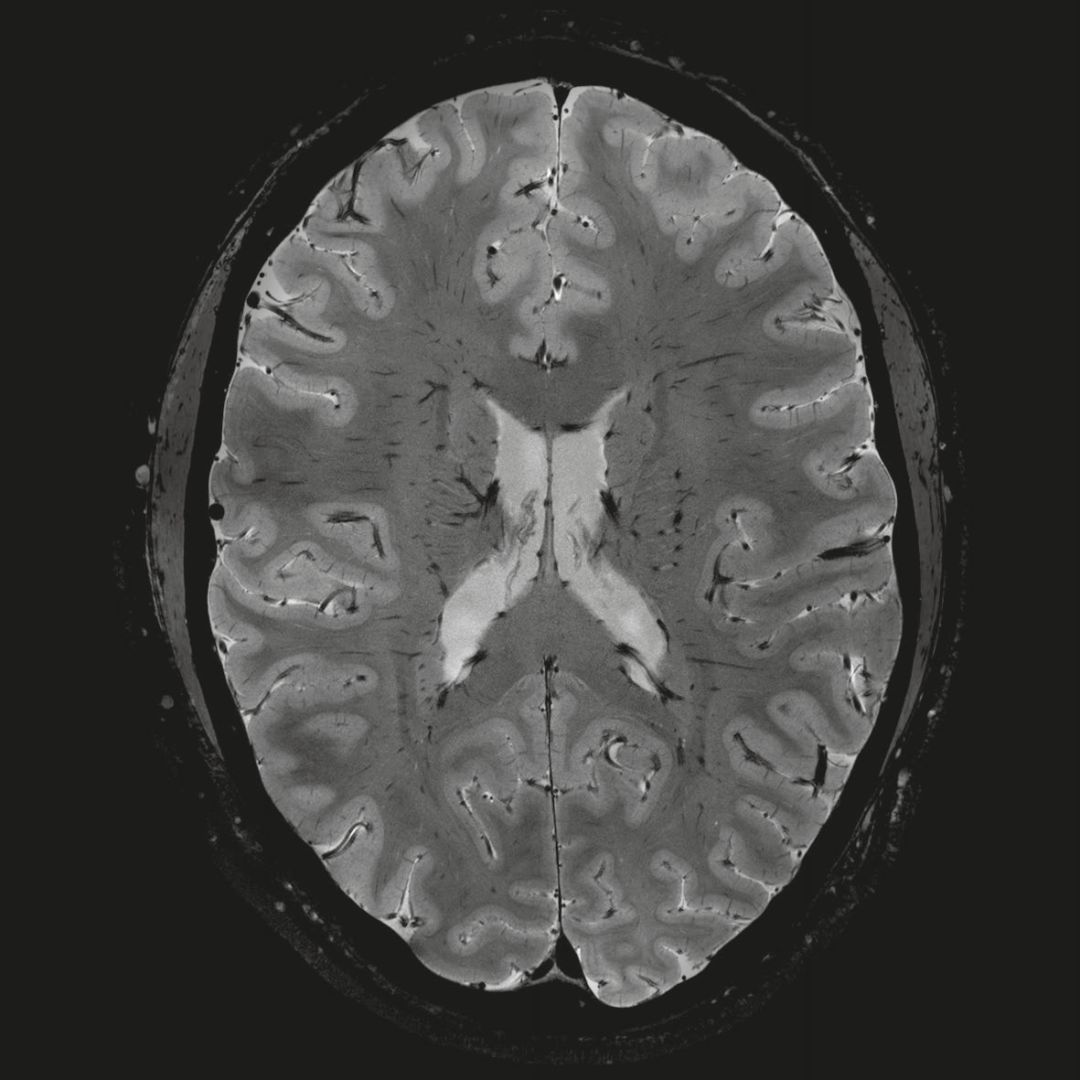

0.8毫米的各向同性分辨率:精確劃分灰質和白質

超精細的解剖細節(jié):T2對比

0.17 x 0.17 x 0.8毫米分辨率超高。